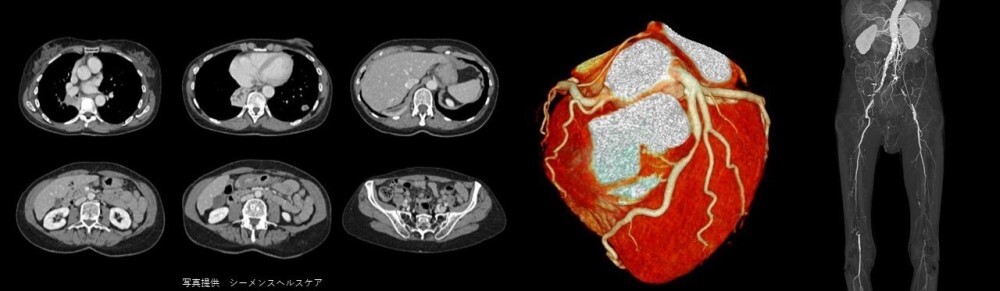

CT検査

CT検査とは、人体の輪切り画像をコンピュータによって再構成して、全身を調べることができます。造影剤を使用することにより、腫瘍などの病変が分かりやすくなり、血管走行を把握することも可能です。

写真:CT1

写真:CT2